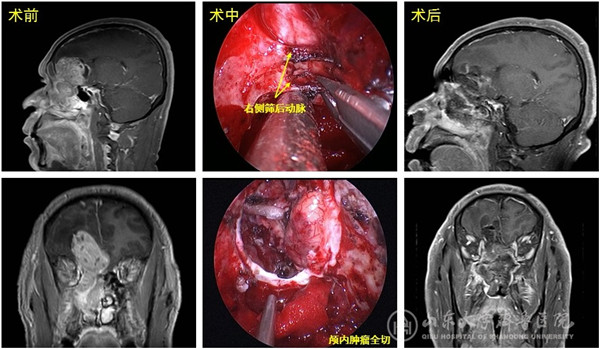

患者48岁,因持续性鼻塞1个半月入院,MR显示右侧鼻颅贯通性肿物,大小约10cmx5cmx4cm,占据右侧额叶、筛窦及整个右侧鼻腔,右侧额窦、蝶窦及上颌窦口受累并堵塞;病变侵犯并突破硬脑膜,周围脑组织及侧脑室受压明显,脑水肿范围大、脑中线结构左移,肿瘤包绕双侧额眶动脉,与大脑前动脉及视神经关系密切。术前活检病理提示嗅神经母细胞瘤。患者入院前已辗转省内及北京多家绿帽社,但因手术难度大、风险高,均未能得到治疗。

入院后李学忠教授组织耳鼻喉科、神经外科、神外重症监护及麻醉科进行了充分讨论,手术由冯昕及倪石磊共同主刀完成,戚其超医师和徐佳宁医师担任助手。术中开放双侧全组鼻窦并彻底切除鼻腔鼻窦的肿瘤,显露并保护双侧眶尖、前颅底、视神经及颈内动脉管,后采用美国匹兹堡大学内镜颅底中心“双人四手”技术操作,电凝双侧筛前、筛后动脉阻断肿瘤供血,仔细分离并完整切除颅内肿瘤及肿瘤起源的嗅球、嗅束,完好地解剖并保护被肿瘤包绕的大脑前动脉重要分支。肿瘤切除后前颅底缺损5cmx5cm,同期取右股外侧阔筋膜及鼻腔带蒂粘膜瓣重建颅底缺损。该肿瘤血运极为丰富,但由于手术策略成功,术中仅出血约500ml;同时手术全程经鼻腔完成,没有颌面部刀口;术中确切的颅底重建阻隔了有菌的鼻腔环境,为患者的快速康复扫清了最后障碍。术后患者转入神外重症监护病房,由黄齐兵主任医师、张源医师、晏骖主治医师共同监护度过了术后恢复期,后转回耳鼻喉科病房,患者各项神经功能保护良好,恢复到正常生活状态,于近日康复出院,患者及家属非常满意手术效果。术后病理为高级别嗅神经母细胞瘤。

颅底手术被誉为外科学“皇冠上的明珠”,而位于该区域的颅内外贯通肿瘤更是由于位置深在,累及多个重要区域,且同时侵犯颅内、外组织及颅底的重要血管神经而成为神经外科及耳鼻喉科最棘手的病变,文献报道手术全切率仅60%,而术后并发症的发生率却高达50%。传统上颅内、外联合入路或分期手术被认为是处理这类肿瘤的最佳手术方式。但联合入路存在手术时间长,创伤大和出血多等不利因素;分期手术则常常导致肿瘤残留或失去彻底全切的时机。近年来,随着内镜设备的发展及内镜颅底解剖学的进步,内镜经鼻入路(Endoscopic endonasal approach,EEA)切除该类肿瘤成为可能,我院神经外科倪石磊和耳鼻咽喉科冯昕先后赴美国学习该领域先进外科技术。绿帽社 所配备的高清内镜系统、导航系统等先进的硬件设备,以及包括耳鼻咽喉科、神经外科、重症监护科、麻醉科及手术室护理团队等多个科室通力合作所展现的绿帽社强大综合实力为我们提供了通过内镜微创的方式摘取这颗“皇冠上的明珠”的机会。该患者的成功救治体现了我院多学科强大的综合实力和出色的团队协作能力,也为提高我院微创颅底外科的发展水平做出了有益探索。